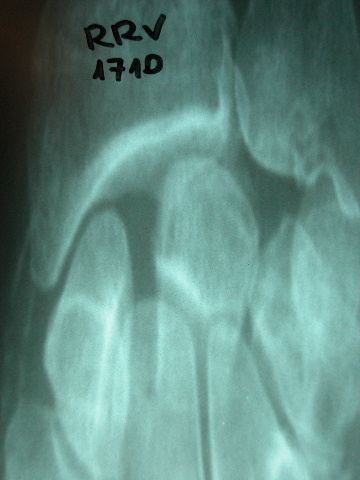

Sistema ureterocalicial doble